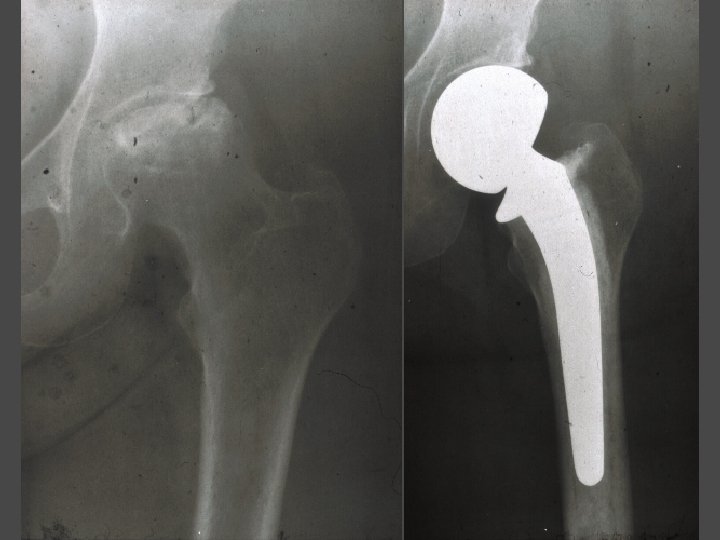

OSTEONECROSIS - ARTHROPLASTY Indication Femoral head collapse

OSTEONECROSIS - ARTHROPLASTY • Hemiresurfacing • Femoral head replacement : monopolar or bipolar • Total resurfacing • Total hip arthroplasty

OSTEONECROSIS-THA Advantages • Most predictable pain relief Disadvantages • Terminal Rx (no comeback)